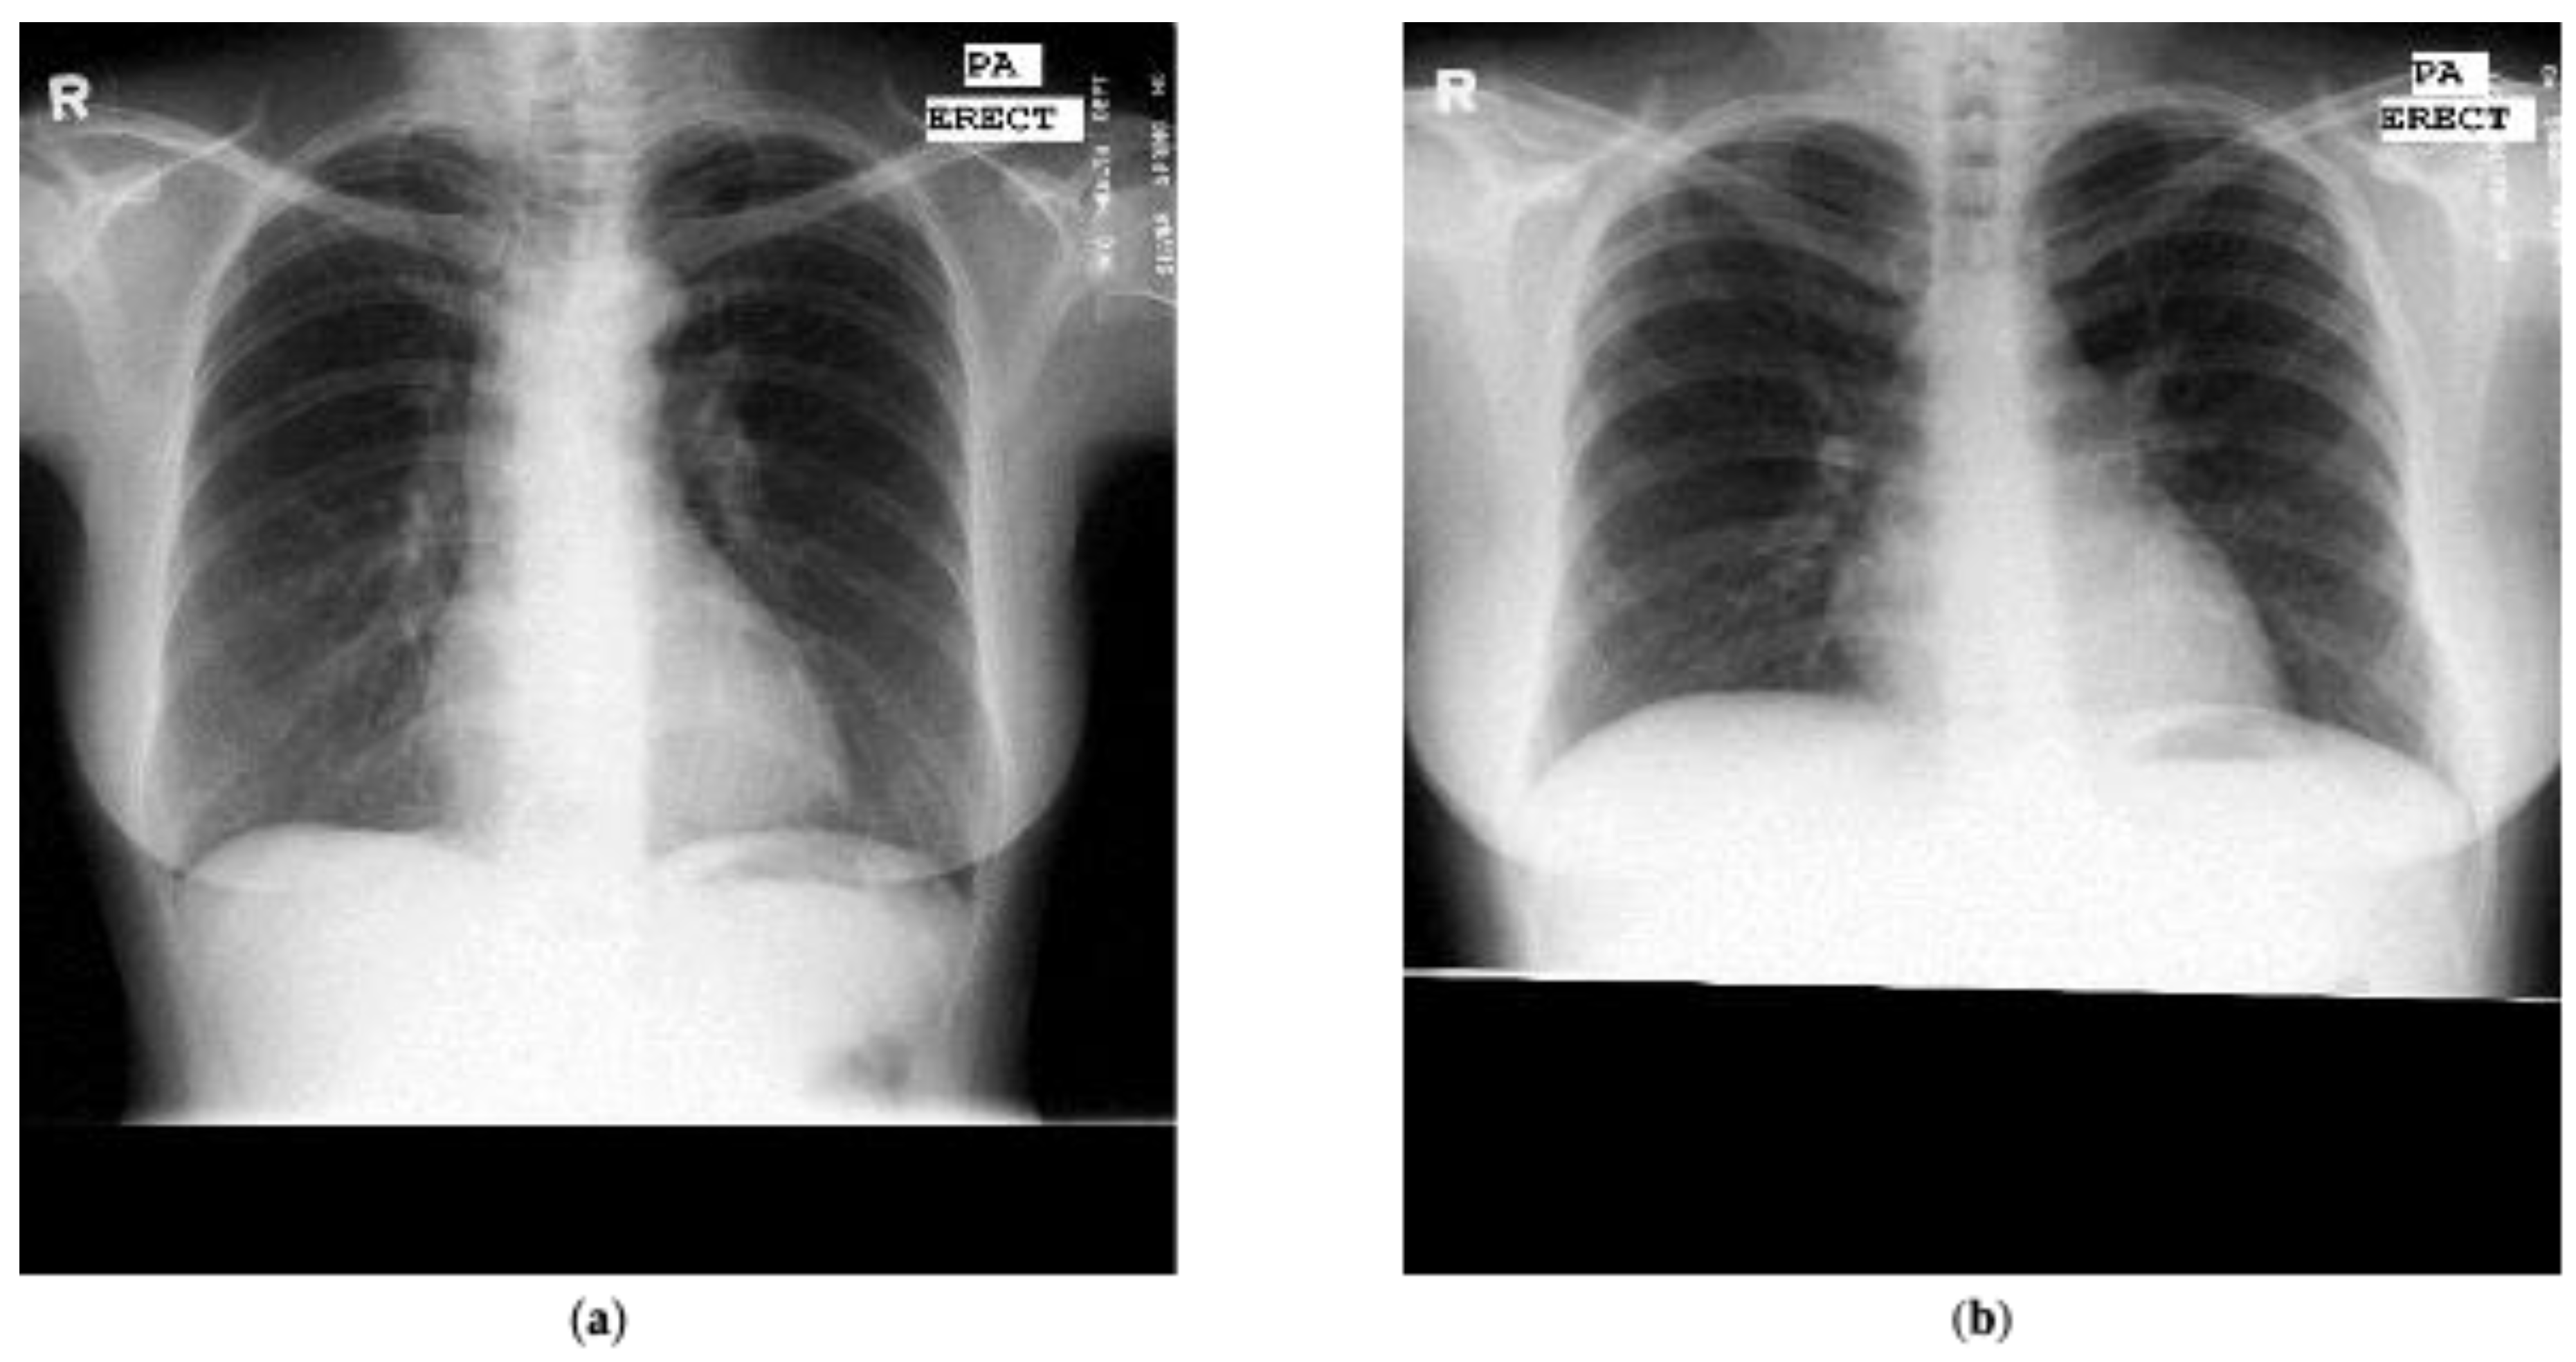

We also utilized a publicly available Shenzhen dataset marked by radiologists for the detection of tuberculosis [44,45,46,47]. This dataset was composed of 662 annotated chest radiographs with 336 marked as tuberculosis and the rest marked as normal. Figure 2 presents two examples presented in the Shenzhen dataset that have been marked as normal and tuberculosis, respectively, by radiologists. In addition, manual lung masks were publicly available for 566 cases in the Shenzhen dataset. Note that we included only those cases for this research.

Figure 2. Chest radiograph examples from the Shenzhen dataset marked by radiologists: (a) normal; (b) tuberculosis.